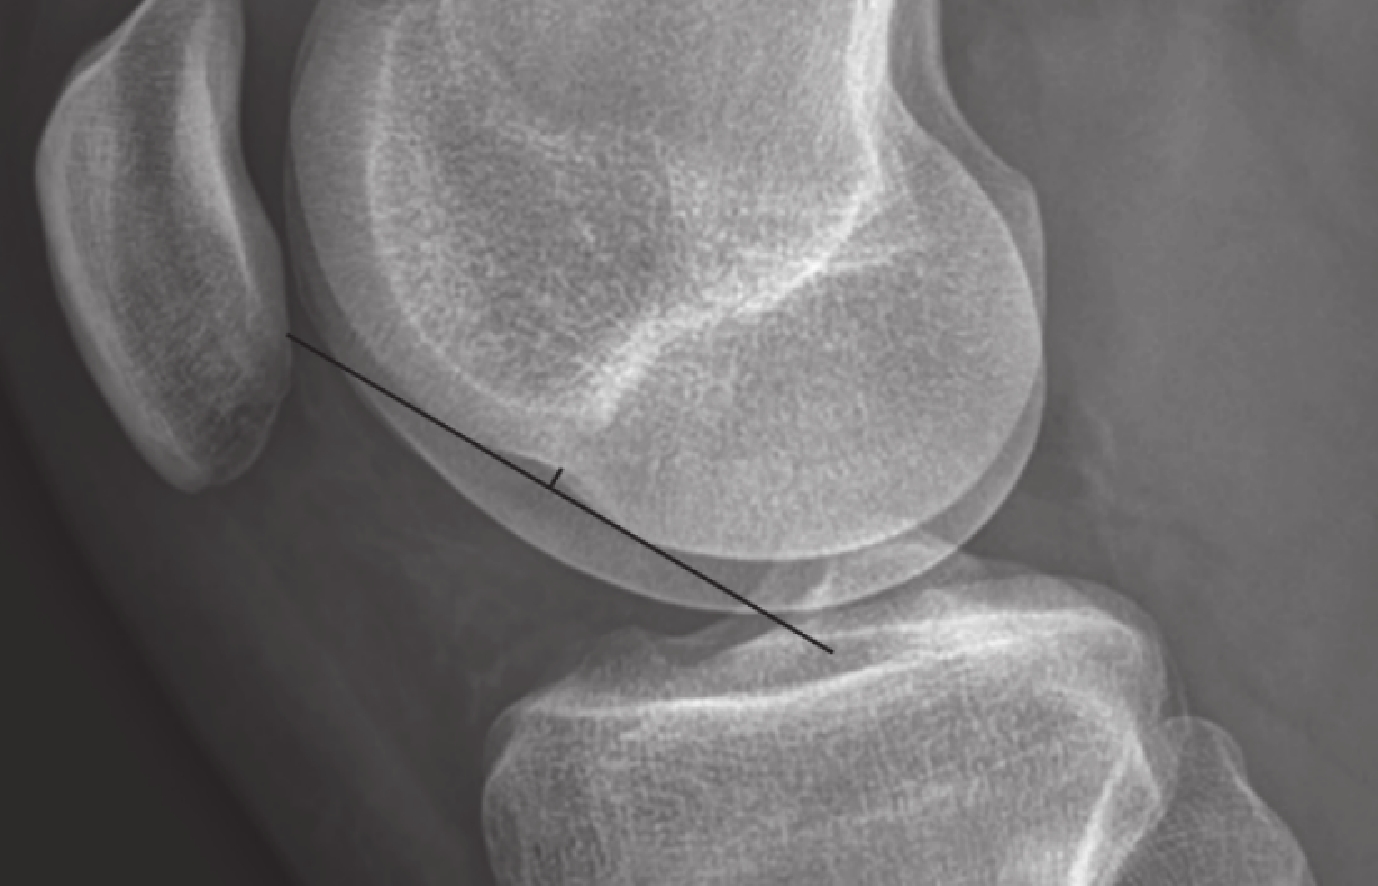

雖然 LFNS 被認為是 ACL 斷裂的間接征象,但其定量診斷標準尚未統一。目前,大多數研究選擇在膝關節側位 X 線片或 MRI 矢狀位圖像進行測量。具體步驟:首先,在膝關節側位 X 線片或 MRI 矢狀位圖像尋找切跡最深的層面,沿股骨外側髁輪廓作 1 條與切跡相接的切線,再通過切跡最深處作 1 條該切線的垂線,該垂線長度即為 LFNS 最大深度(圖 1)。該測量方法簡便且便于定量分析,測量值越大提示 LFNS 越顯著。此外,也有研究提出另一種定量評價方法,即在膝關節側位 X 線片上將 Blumensaat 線延長至外側髁輪廓并相交于一點,以該點與 LFNS 切跡邊緣的距離作為定量診斷標準,但該方法應用較少[25-26]。